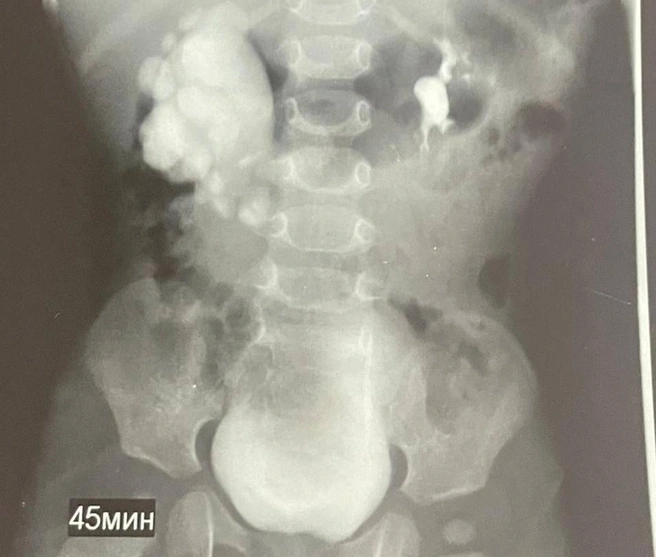

Специалисты заметили неладное еще на этапе внутриутробного развития. УЗИ выявило расширение почечных лоханок. Сразу же после рождения за мальчиком стали пристально наблюдать. К сожалению, не зря, потому что ситуация стала ухудшаться. Обследование в урологическом отделении весной этого года подтвердило, что у ребенка развился гидронефроз.

«Это состояние, при котором моча не может нормально отходить из почки, застаивается и буквально распирает ее изнутри. Без операции почка могла бы просто перестать функционировать», — сообщили в городской клинической больнице скорой медицинской помощи Ставрополя.